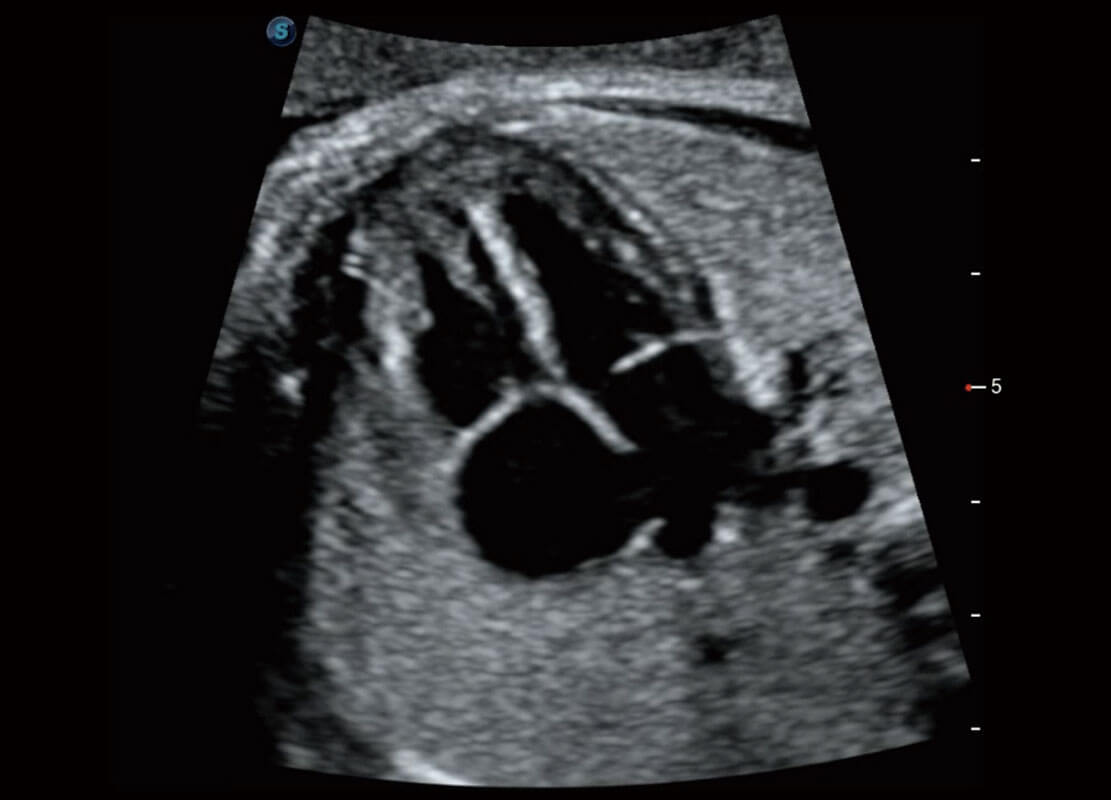

P60搭载一系列胎儿心脏成像技术,实现精细的胎儿心脏评估。

右室双出口

胎心容积成像